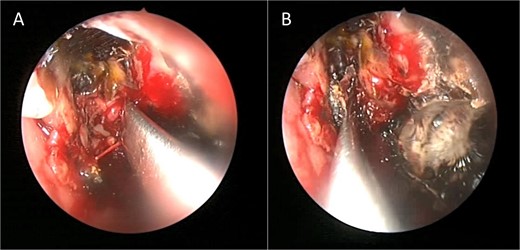

Intra-operative endoscopic view (A) right middle meatal antrostomy showing fungal debris, (B) clean right maxillary sinus after removal of the debris.

Intra-operative endoscopic maxillary examination (A and B) showing invasive fungal debris.